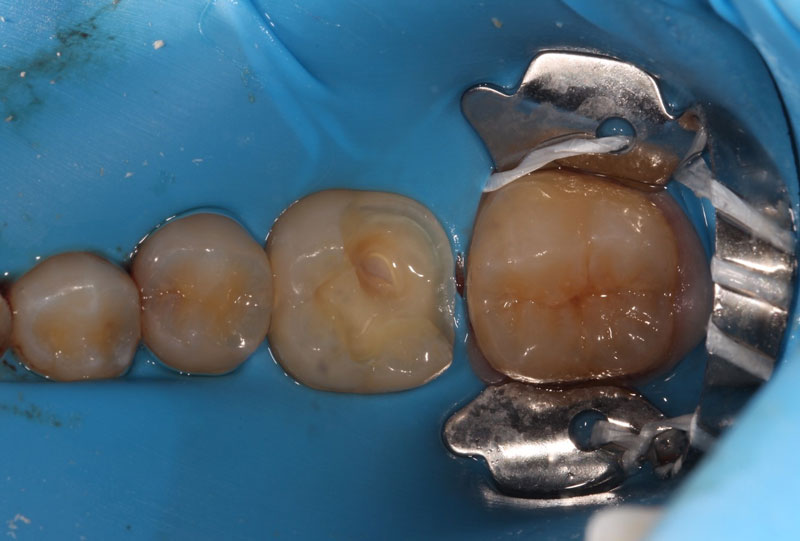

Another key factor is isolation. In general, when a carious lesion is near the pulp chamber, it is advised to utilize rubber dam isolation. This helps minimize any contaminants in the preparation and simplifies the transition to endodontic therapy if pulp exposure occurs, which necessitates it.

A direct pulp cap exposes a portion of the pulp tissue. This can occur due to traumatic or carious pulp exposures. In the past, when a tooth’s pulp was exposed, it almost always led to endodontic therapy. However, direct pulp capping may be feasible in specific clinical situations with modern materials that can help maintain pulp vitality, such as MTA and similar bioceramics.